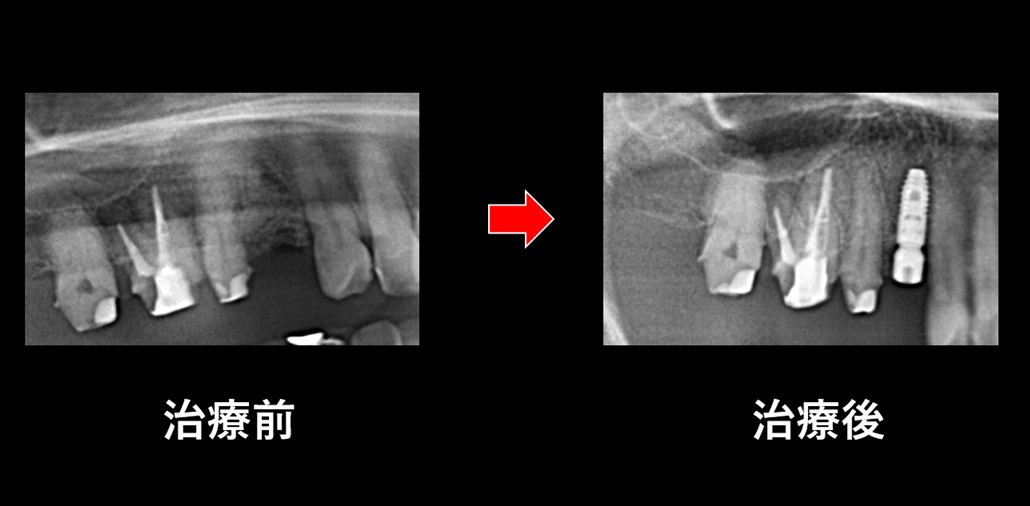

先日は、当院で行いましたインプラント手術の症例をご紹介いたします😊

右上奥歯「4番」へのインプラント埋入でした。

重度に進行したむし歯の歯のため、抜歯時に骨造成処置を事前に行いました。

(インプラント埋入前に4ヵ月骨造成期間を置きました。)

手術は特に問題なく、比較的短時間で予定通りに埋入を終えることができました💡

ここから数か月かけて、インプラントと顎骨がしっかり結合する「オッセオインテグレーション🦴」を待ち、その後に最終補綴(かぶせ物治療)を行っていく予定です✨